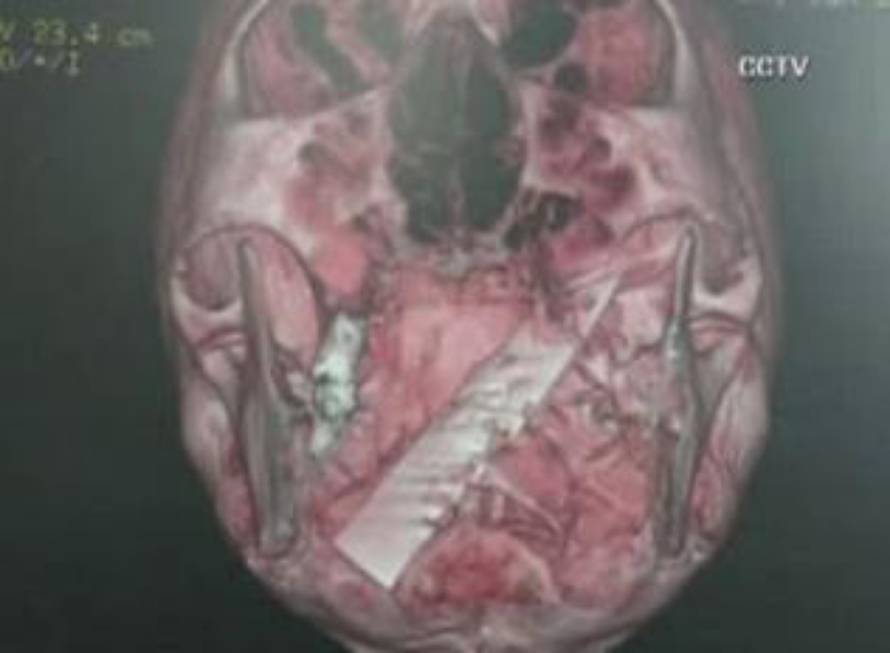

Muškarca su prije više od četiri godine uboli nožem u glavu tijekom jedne pljačke. Liječnici nisu primijetili da mu je nož 'zapeo' u mozgu. Operirali su ga prošli tjedan